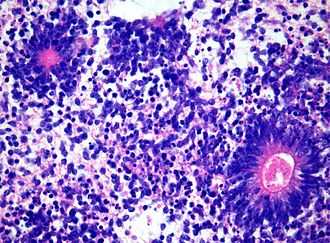

На вскрытии в брюшной полости обнаружено опухолевидное кистозно-солидное образование, сдавливающее мочеточники и петли толстой и тонкой кишки. Опухоль размерами 85×60×40 мм имела неправильную форму и бугристую поверхность (рис. 1, а). На разрезе множество кист, заполненных слизистым, серозным и геморрагическим содержимым. Солидные участки белесовато-серого и желтоватого цвета, разной степени плотности, с очаговыми кровоизлияниями. Гистологически наиболее значимым компонентом опухоли была незрелая нейроэпителиальная ткань, представленная нервными трубочками и псевдорозетками из темных гиперхромных столбчатых клеток, формирующих многорядные структуры с многочисленными митозами (рис. 1, б), а также формирующиеся сосудистые сплетения (рис. 1, в) и элементы незрелой веретеноклеточной стромы. Энтодермальный компонент представлен многочисленными кистами, выстланными эпителием кишечного типа, встречающимися в 1—2 полях зрения каждого среза (рис. 1, г). Часть опухоли состояла из зрелой мезодермы (хрящевая, гладкомышечная, жировая ткань) и энтодермы (кисты и железистые структуры, выстланные переходным цилиндрическим и призматическим эпителием). Незрелые энтодермальные элементы представлены также тканью печени и почечной бластемой (рис. 1, д, е). Патогистологическое заключение: незрелая тератома забрюшинного пространства (2-я степень незрелости, high-grade).

Рис. 1. Тератома забрюшинного пространства.

а — макроскопическая картина опухоли кистозно-солидного строения; б — незрелые элементы нейроэктодермального происхождения; в — формирующиеся сосудистые сплетения; г — кисты, выстланные эпителием кишечного типа; д — неполноценные печеночные балки; е — незрелая ткань почек. Окраска гематоксилином и эозином, ×400.